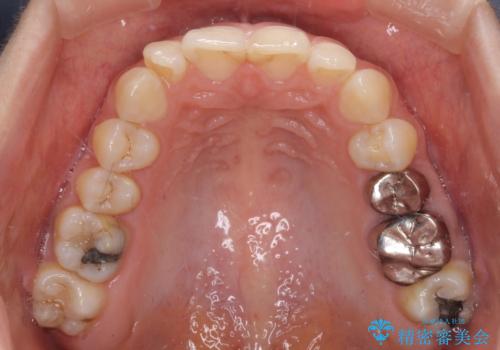

- 下顎の前歯が隠れていることと、デコボコを気にして来院された患者様です。

目立ちにくい装置を希望されていたため、ワイヤー装置とインビザラインを提案したところ、インビザラインを希望されました。

銀歯やムシ歯処置の必要な歯が奥歯にあり気になっていたので、矯正治療の途中でセラミッククラウンへ変更し、その後歯列を仕上げていくこととしました。